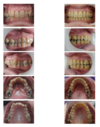

Les types de malocclusions qui peuvent être corrigés

Vous avez probablement entendu parler des dents chevauchées (dysharmonie dento-dentaire par défaut), des espaces entre les dents (dysharmonie dento-dentaire par excès) ou encore de la mâchoire supérieure qui est trop en avant ou trop en arrière par rapport à celle du bas.

Tous ces problèmes de dysharmonie de la mâchoire sont appelés des malocclusions et peuvent être associés ou non à un mauvais alignement des dents.

Les dents chevauchées

Les espaces entre les dents

La béance dentaire

La morsure croisée